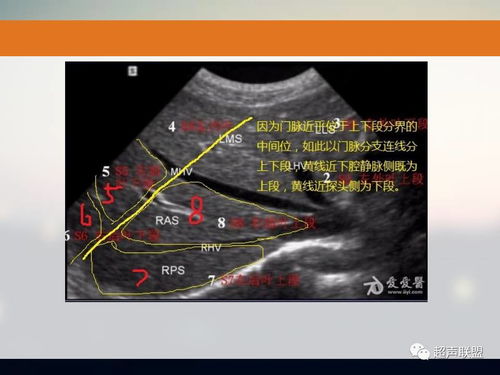

- CT检查:首先找出肝脏的三大静脉:肝中静脉、肝左静脉、肝右静脉;找出门静脉及其分叉部位。门静脉分叉可以区分上段和下段,即肝S5/S8、S6/S7,门静脉分叉以上为S8、S7;肝右静脉和肝中静脉之间是右前叶,肝右静脉以后是右后叶;一般规律,从CT上看,最先看到的是S8,然后是S2、3,肝左外叶以肝裂为界,比较容易辨认,左内叶为肝裂和肝中静脉之间区域,胆囊往下的层次是S5,最后的层面一般是肝S6,下腔静脉和门静脉夹着的是尾状叶,即S1。